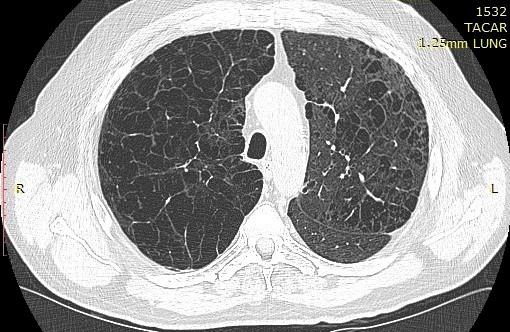

Eficacia del rastreo de cáncer de pulmón en poblaciones seleccionadas

13 septiembre 2021

Los resultados del estudio británico UKLS muestran reducción de la mortalidad por cáncer de pulmón a partir del rastreo en pacientes de alto riesgo con una única tomografía computada de baja dosis. Un metaanálisis de nueve ensayos aleatorios proporciona un apoyo inequívoco para la detección del cáncer de pulmón en grupos de riesgo identificados. The Lancet Regional Health Europe, 11 de septiembre de 2021.